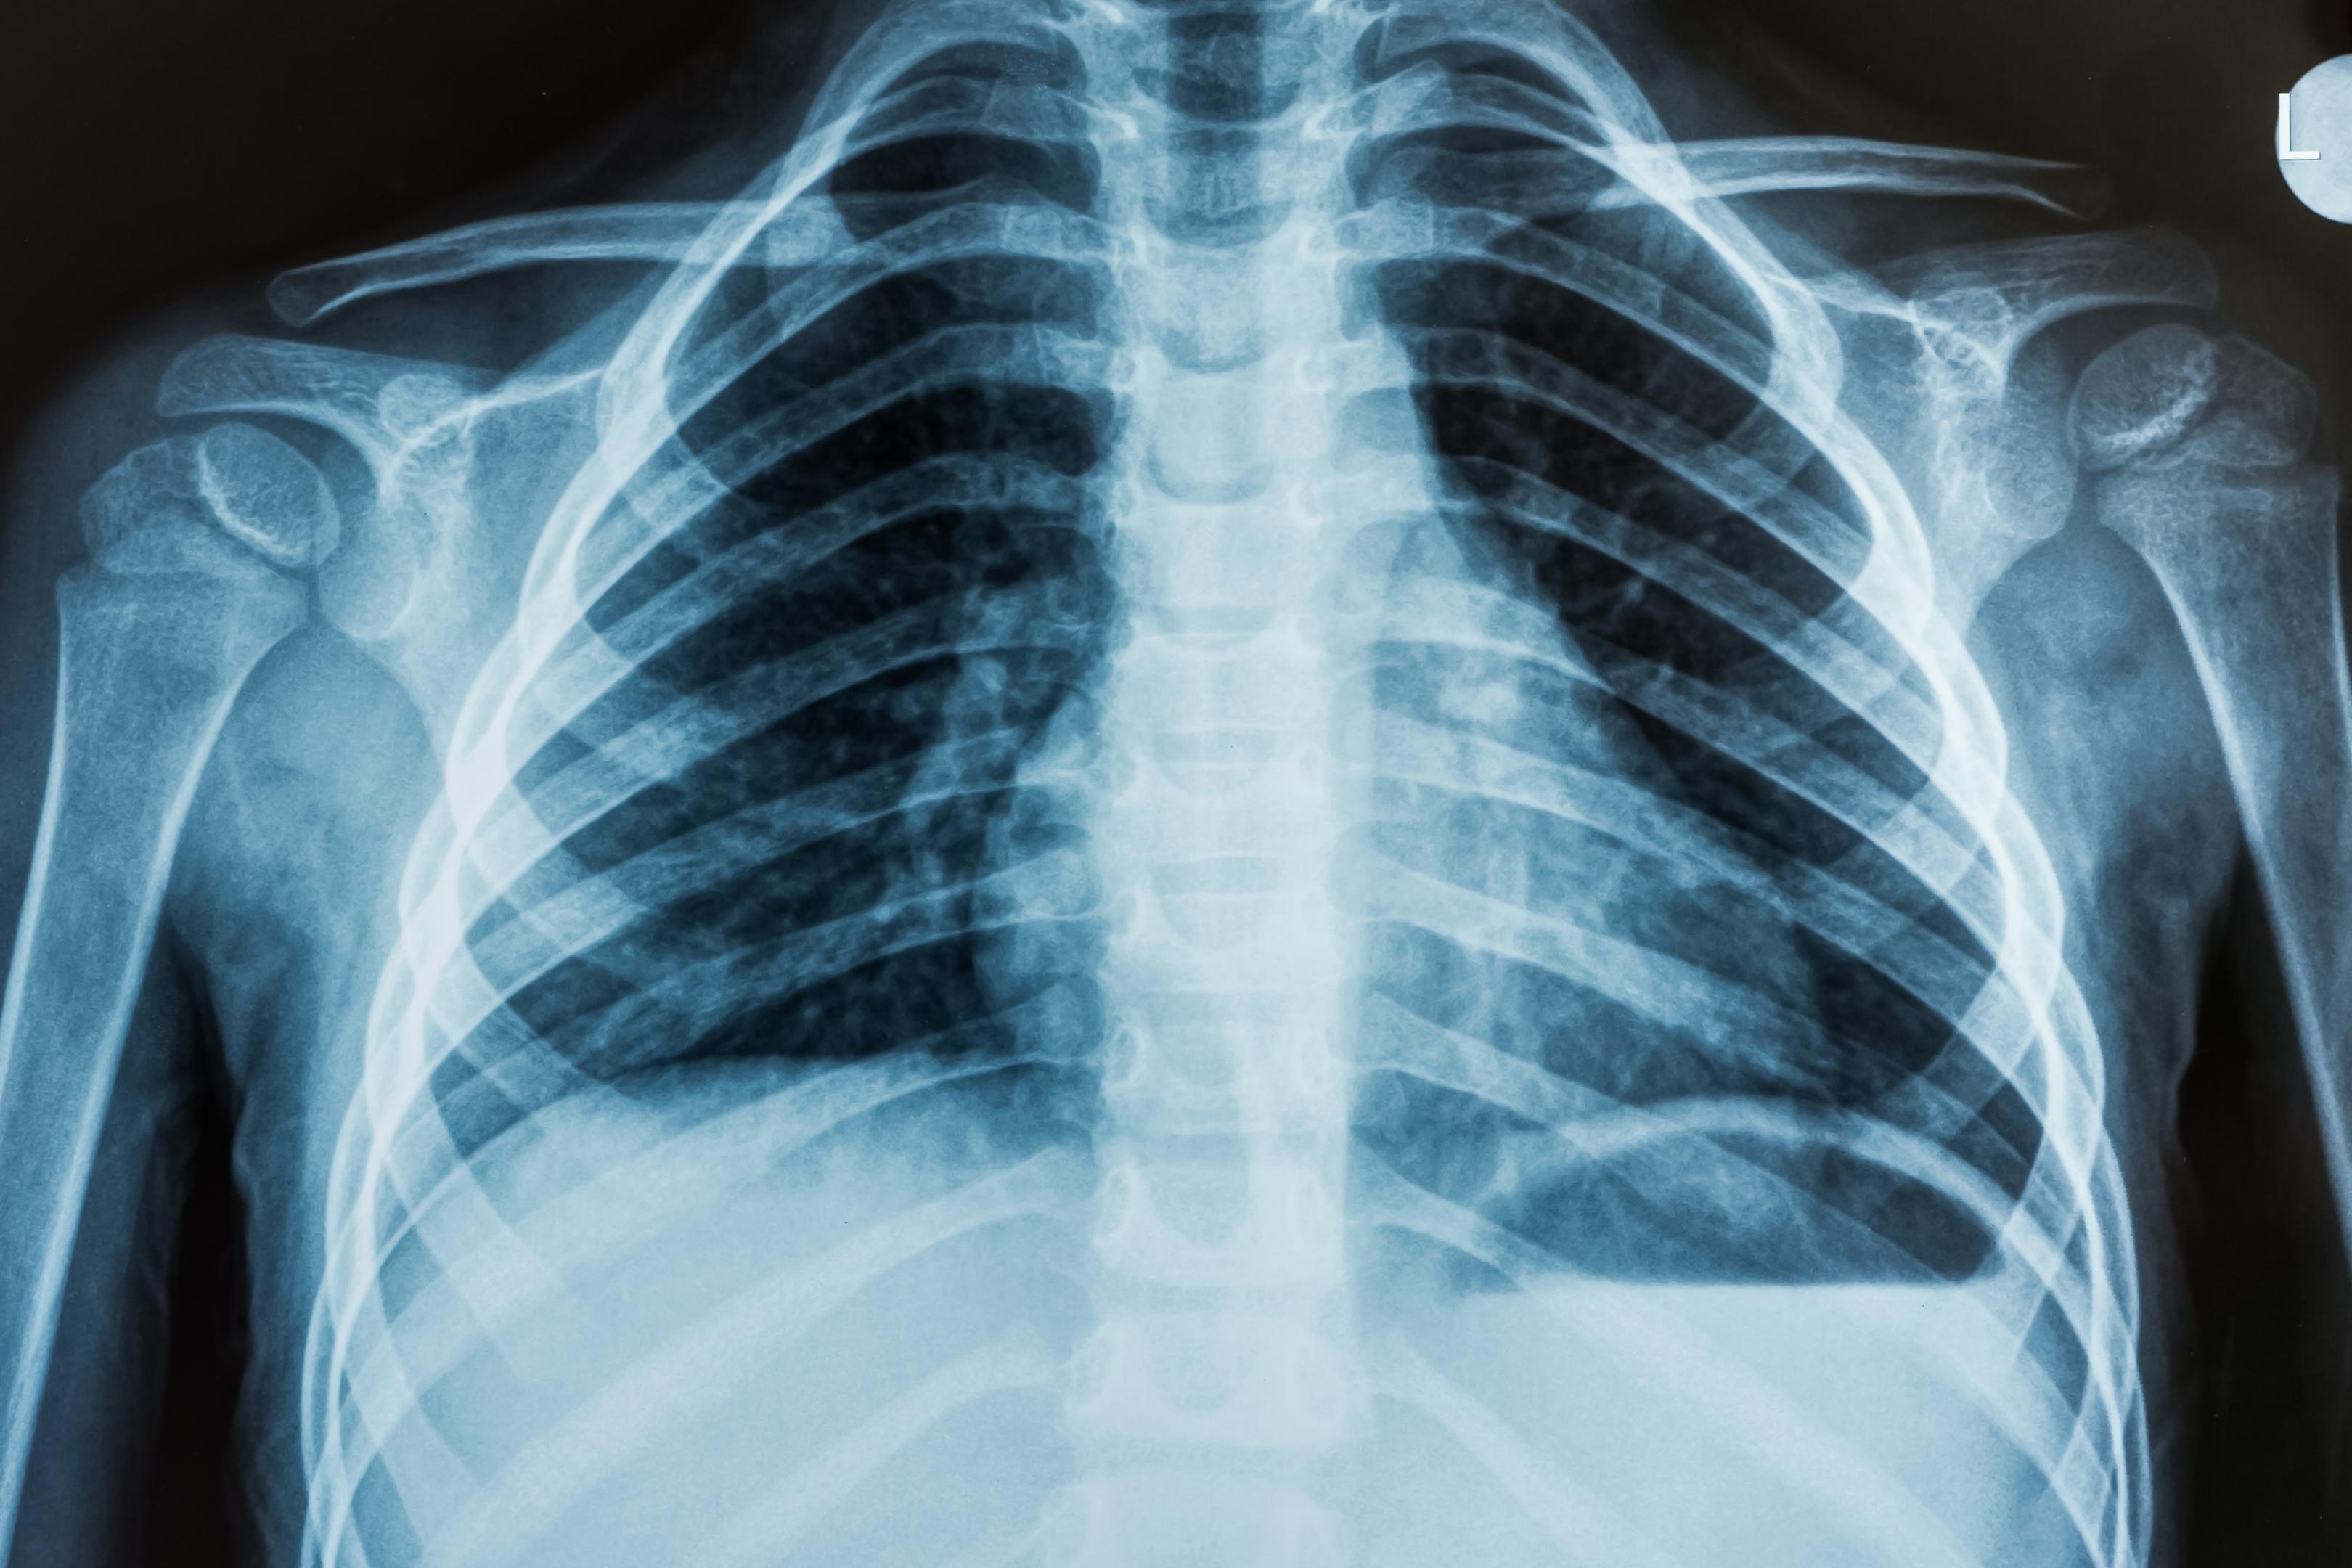

Rapid chest X-ray imaging for respiratory conditions, pneumonia, and cardiac assessment.

The Radiology department at Shaista Medical Center provides advanced diagnostic imaging services with rapid turnaround times. Our X-ray facilities are equipped with modern imaging equipment to produce high-quality images that support accurate diagnosis across all medical specialties.